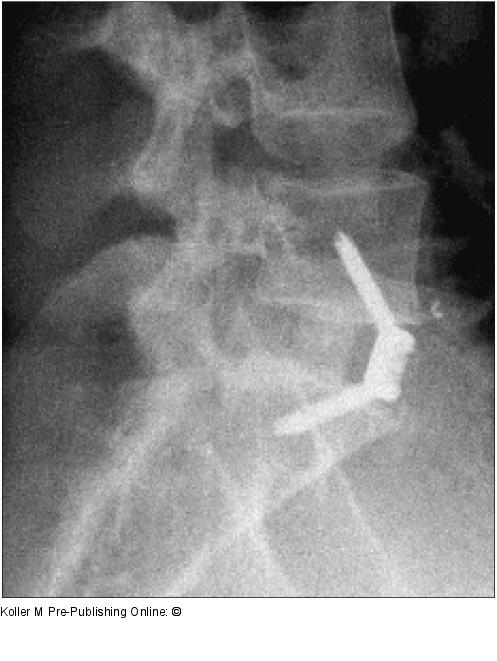

Abbildung 10: Spondylodese

Ventrale Spondylodese L5/S1 mit verschraubbarem Cage |